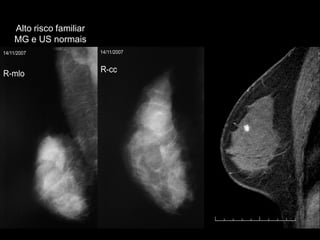

Alto risco familiarMG e US normais

•Taxa de cânceres de intervalo < 10%.

•50% tratavam-se de CDIS ou carcinomas invasivos < 1 cm.

•79-88% sem envolvimento de linfonodos axilares.

Rastreamento do câncer de mamaCaracterísticas tumorais